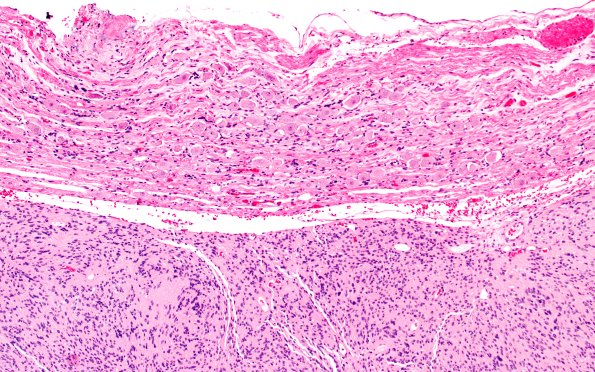

30B2 Schwannoma (Case 30) H&E 10X A

Higher magnification of image #30B1. (H&E)